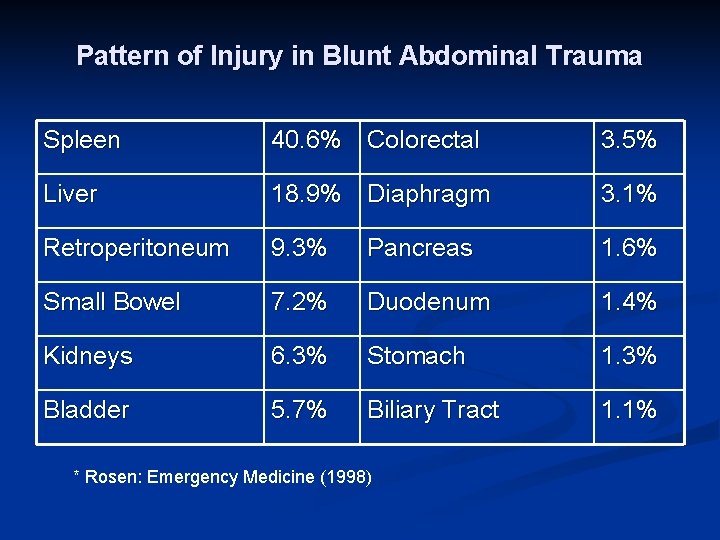

Pattern of Injury in Blunt Abdominal Trauma Spleen 40. 6% Colorectal 3. 5% Liver 18. 9% Diaphragm 3. 1% Retroperitoneum 9. 3% Pancreas 1. 6% Small Bowel 7. 2% Duodenum 1. 4% Kidneys 6. 3% Stomach 1. 3% Bladder 5. 7% Biliary Tract 1. 1% * Rosen: Emergency Medicine (1998)